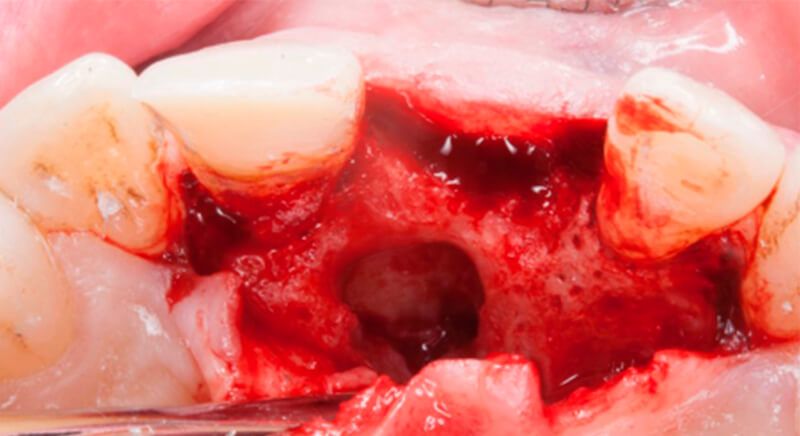

Once tooth 2.1 had been extracted, it was decided that it was not advisable to place an implant immediately as the bone conditions were not ideal and the gum did not have sufficient thickness. We opted for a treatment to preserve the socket and to delay implant insertion.

The socket was filled with a xenograft after the extraction and a graft of connective tissue was placed in the vestibular area of the two upper central incisors.

The tissue with epithelium was taken from the palate and de-epithelialized outside of the mouth. This obtains a lamina propria graft with better density and quality than if it were obtained with a single incision to the palate.

Once the hard and soft tissues had healed, 6 months after the surgery, a good volume remained in the vestibular area. It was then that we could consider an implant, using guided surgery to ensure it was placed in the correct three-dimensional position.